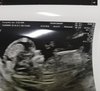

U mnie na usg teraz wyglądało to tak:

Widać gdzie lekarka pokazuje kursorem ten owy „wyrostek” na płasko a wręcz skierowany do dołu.

IMG_2333.JPG